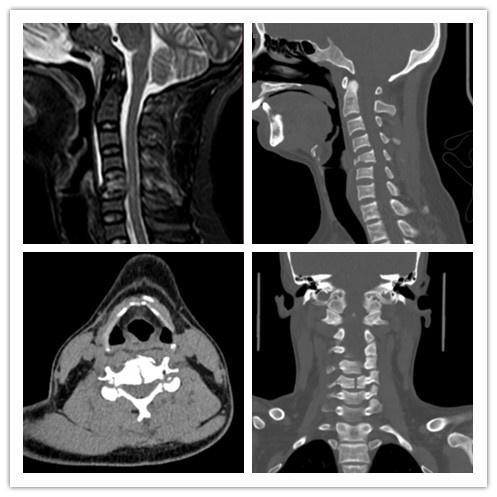

患者,男性,35岁,因“颈椎骨折”收住我院。患者因颈椎骨折,颈椎丧失稳定性,若不及时治疗会对颈部脊髓产生继发损伤。张海鸿教授团队全面评估患者病情,对患者进行颈5椎切除3D打印人工椎体置入融合术。手术历时1小时,术后患者颈部疼痛明显缓解,四肢活动良好,颈部稳定性及生理曲度恢复,次日拔除引流管下地行走并于当日出院。

近年来,3D打印技术在临床医疗中应用,3D打印此技术可以根据患者的影像学参数进行定制治疗方案,制作出更加接近患者自身形态的椎体。此外,3D打印人工椎体局部形态结构模拟松质骨,便于更好的骨长入。材质的弹性模量介于人体骨模量阈值范围(人体骨:5-27Gpa,3D打印椎体:14Gpa),减少了内置物对接触骨的损伤,其假体表面图层有良好的骨诱导作用,增加骨张入速度。该假体的使用较以往术式中置入钛笼降低了椎体塌陷的风险,较使用自体髂骨,减少了取骨区域的疼痛和感染机率,给病患带来了更好的治疗体验。该技术的采用,代表着颈椎骨折治疗进入了3D打印新时代。